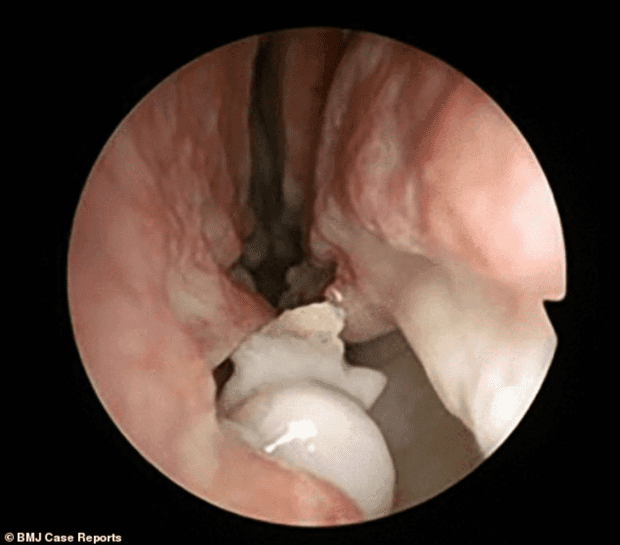

Allí, los profesionales descubrieron que en el interior de sus fosas nasales había crecido un diente. Tras realizarse los estudios correspondientes, se constató que es deformidad se trabaja era en realidad un tumor.

Según dio a conocer el centro médico, esta condición se la identifica como hiperdoncia o dientes supernumerarios y afecta a sólo el 4 por ciento de la población humana, pero que crezca con un desvío hacia arriba en el 0.1 por ciento de las personas.